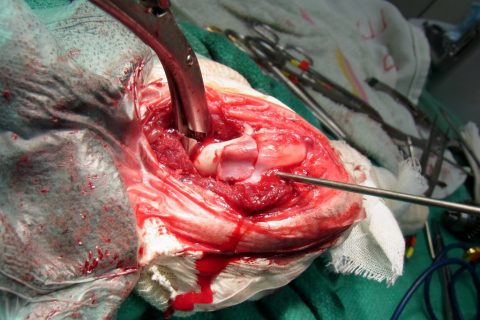

治療

大腿骨遠位端骨折は、比較的手術が難しい骨折です。当院では院内で矢状ピンを作成して手術しています。

治療結果はかなり良い状態です。